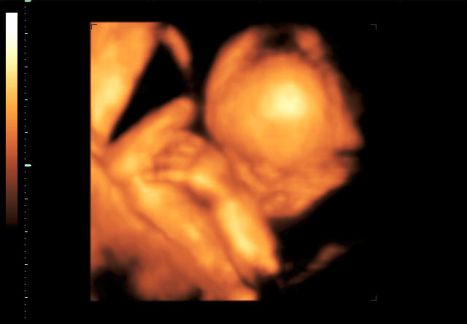

Bence 18 hetesen